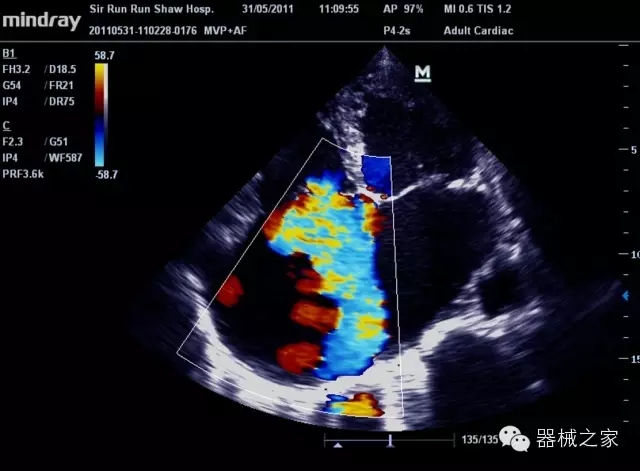

臨床圖片賞析

產(chǎn)品特點(diǎn)

·裝載有采用Multi-Core多核處理的非嵌入式平臺,成像效率大大提高,并且能夠給用戶帶來高速、多任務(wù)并行信號處理體驗(yàn);

·優(yōu)秀的圖像效果、強(qiáng)大的功能體驗(yàn)、豐富的探頭選擇、合理的便攜式設(shè)計,全中文顯示及病人管理界面,使得M7在任何場合、任何時候都能快速響應(yīng)更好的心血管、腹部、婦產(chǎn)、小器官等常規(guī)超聲檢查以及肌骨、神經(jīng)、顱腦、術(shù)中等新興領(lǐng)域的使用需求;

8倍波束并行處理系統(tǒng)

·在便攜式緊湊平臺上采用更多倍波束并行接收信號處理模式,無論二維還是彩色血流圖像狀態(tài)下,擁有更靈敏的回波頻移捕獲能力,大大提高時間分辨率,尤其使得心血管表現(xiàn)更為突出;